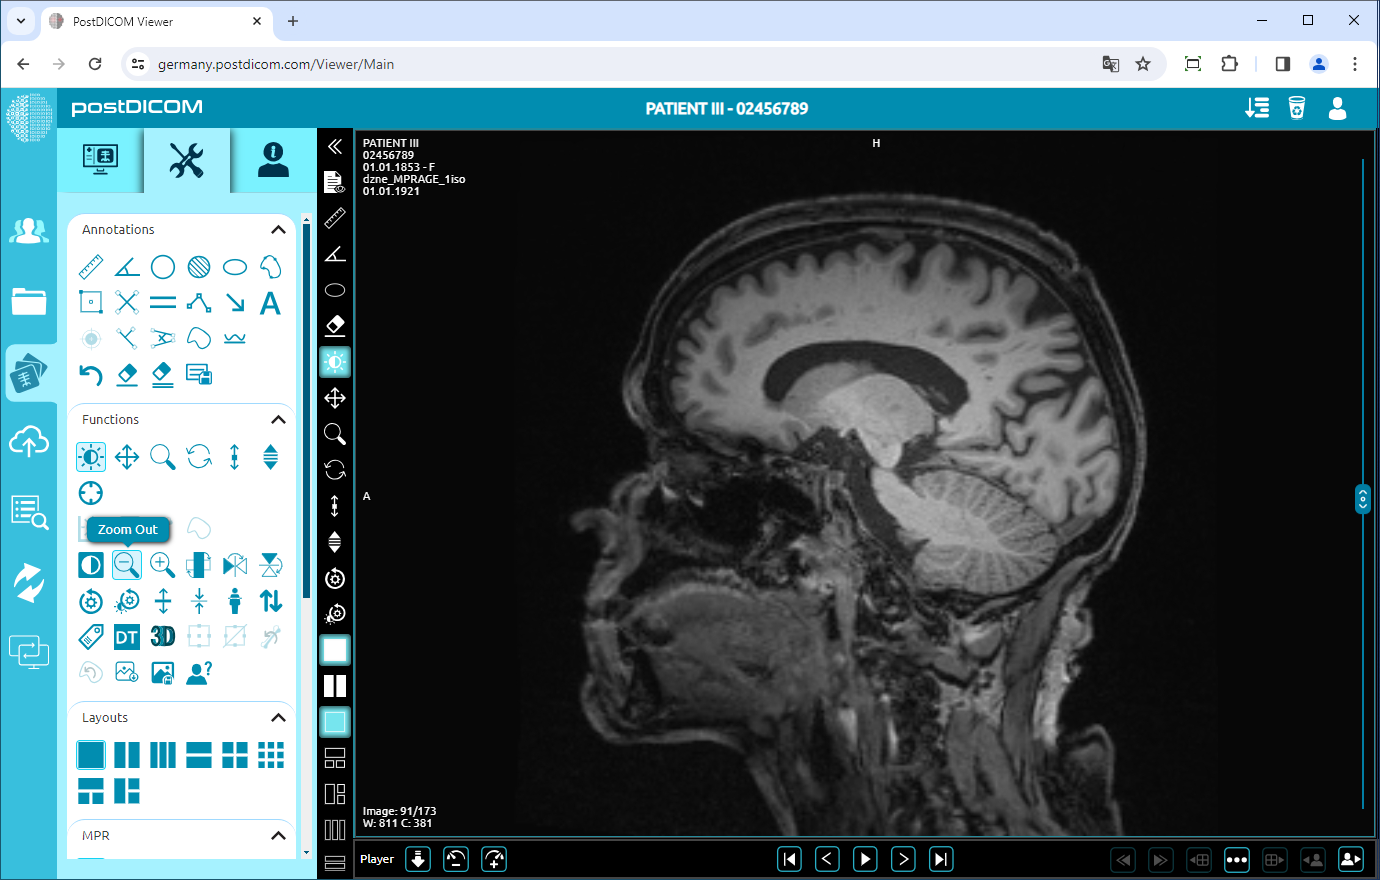

To zoom out the image by one level, click on “Zoom Out” icon on the left side of the page.

After clicking, you will see that the image will be one level smaller. The more you click, the image will be smaller.